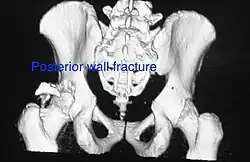

Posterior wall fracture as seen on 3-D CT scan -

Posterior wall fracture fixed with screws and plate -